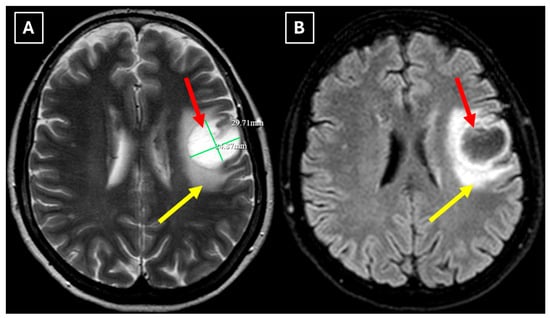

Figure 1. Native head CT without I/V contrast Images (A,B) show a. Hypodense lesion in the left hemisphere, basal parts of the frontal lobe. Measuring up to at least 3.5 cm in maximum size, with mild perifocal edema. Red arrow—indistinct formation.

One week later, a brain MRI with intravenous contrast was performed, which revealed a well-defined subcortical lesion approximately 3.5 cm in diameter in the posterior basal parts of the left frontal lobe, accompanied by perifocal edema and sulcal effacement (Figure 2). No pathological contrast enhancement was observed (Figure 3). No other white matter lesion was identified to suggest signs of leukodystrophy, and no hemosiderin deposits were identified in the brain or meninges (Figure 3). Given the T2/FLAIR mismatch (Figure 2), the most likely diagnosis was infiltrative low-grade astrocytoma. The patient received mannitol anti-edema therapy, resulting in clinical improvement and a reduction in neurological symptoms. The case was discussed by a multidisciplinary team (neurologist, neurosurgeon, radiologist, oncologist, and pathologist). Surgical treatment and morphological verification of the tumor were recommended. A day later the patient was discharged from the hospital in a stable condition, with a recommendation to be admitted to the neurosurgery department for surgery in two weeks. She was prescribed dexamethasone tablets of 0.5 mg twice daily on an outpatient basis.

Figure 2. MRI scan of the brain. (A): Axial T2-weighted sequence shows a well-defined, homogenous, hyperintense mass-like lesion in the inferior part of the left frontal lobe, with involvement of the juxtacortical white matter and relative sparing of the cortical gray matter. The lesion measured 37.34 mm × 34.85 mm (AP × LL). Additionally, there is incomplete perifocal edema surrounding the lesion, extending to the white matter and away from the cortex. (B): Axial FLAIR sequence shows the lesion with a relatively more hypointense center and a hyperintense peripheral rim at the lesion margins. A T2/FLAIR mismatch sign was observed, making the likely diagnosis an infiltrative low-grade astrocytoma. All MRI images were acquired with the Philips “Ingenia Ambition X” 1.5T system. Red arrow—indistinct formation, yellow arrow—perifocal vasogenic edema.

Figure 4. Two-week follow-up MRI scan of the brain. (A): Axial T2-weighted image shows a hyperintense and homogenous left frontal lobe lesion with well-defined borders. The lesion decreased from 37.34 mm × 34.85 mm (AP × LL) to 24.87 mm × 29.71 mm (AP × LL). A relatively extensive perifocal edema again persists, involving the white matter with relative spare of the white matter adjacent to gray matter; however, there is no mass effect or midline shift. (B): In the axial FLAIR the lesion appears with a more hypointense center and hyperintense peripheral rim at the lesion margins. Given the observed changes over a 2-week period and the decrease in the lesion’s size, an astrocytoma is considered less likely. Red arrow—indistinct formation, yellow arrow—perifocal vasogenic edema.

Secondly, the presence of a T2/FLAIR mismatch sign in this case, which initially was suggestive of a low-grade astrocytoma, adds diagnostic complexity and underlines the potential for radiological overlap between TDLs and IDH-mutant astrocytomas. One proposed pathophysiological explanation of this overlap is the presence of microcysts and enlarged intracellular space with fluid characteristics similar to cerebrospinal fluid [12,15]. Such components may also be present in both low-grade gliomas and TDLs, resulting in marked T2 hyperintensity and relative suppression on FLAIR sequences. Additionally, this apparent overlap with TDLs may be further explained by shared microstructural changes such as severe myelin loss, reactive gliosis, and accumulation of macrophages, as well commonly seen edema, similarly producing an imaging appearance of (IDH)-mutant 1p/19q non-coded astrocytoma [16]. Studies have also shown that low-grade astrocytomas are among the most frequent histopathological misdiagnoses of TDLs, reflecting their morphological similarity [1]. However, it remains uncertain whether analogous microstructural or fluid-dynamic mechanisms take place in TDLs, since there is no research available that directly investigated the histopathological correlates of the T2/FLAIR mismatch sign in TDLs; in addition, this sign is not mentioned in MRI features of demyelinating diseases. Therefore, its application, specificity, and sensitivity for TDL diagnosis are not established. The underlying mechanisms of TDL pathophysiology also remain incompletely understood, but immune-mediated inflammation with massive infiltration of macrophages and lymphocytes, dysregulated astrocyte signaling, complement activation arising as part of multiple sclerosis leading to exaggerated CNS immune responses, and medication effects such as fingolimod use, as well as its cessation, have all been proposed as contributing factors [6,10,11].

Finally, we provide a high-resolution MRI follow-up of two months’ duration showing near-complete regression of the lesion after corticosteroid therapy. The lesion decreased from 37.34 mm × 34.85 mm (AP × LL) to 24.87 mm × 29.71 mm following two weeks of corticosteroid therapy and after almost two months from the first MRI scan to minimal patchy contrast enhancement (Figure 7D). This marked decrease in the size of the lesion gives strong evidence that a demyelinating rather than neoplastic process is present.

In this case, despite the presence of a T2/FLAIR mismatch sign (Figure 2), several imaging characteristics were more suggestive of a TDL rather than IDH-mutant astrocytoma. The lesion was located in juxtacortical white matter and had cortical sparing, which is unusual for IDH-mutant astrocytomas, since they typically have been shown to infiltrate and expand the cortex. The diffusion restriction at the lesion margin with centrally elevated ADC values was more consistent with reported DWI findings of TDLs and contrasted with the central restriction often seen in gliomas. The mass effect was mild in comparison to the overall lesion size, favoring demyelination rather than neoplasm in this case. Additionally, the lesion had a central vein sign, as described above, a radiological sign supportive of inflammatory demyelination. The combination of cortical sparing, peripheral diffusion restriction, mild mass effect, and the appearance of central vein sign represented strong features that raised suspicion of a tumefactive demyelination lesion.